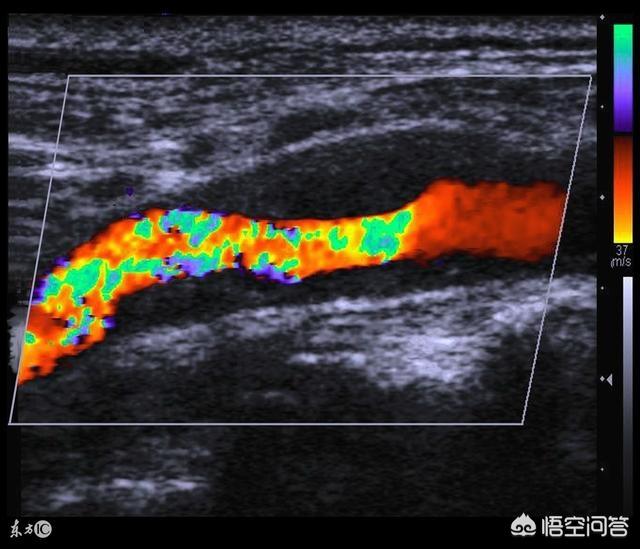

頸動脈プラークは超音波検査によって検出することができ、非侵襲的な検査によってより太い血管を理解する体の能力である。頸動脈は外膜、中膜、内膜の3層に分かれており、正常な状態では内膜と中膜の厚さ(IMT)は0.9mmを超えない。IMTが0.9mmを超えると頸動脈内膜中膜肥厚と呼ばれ、IMTが1.3mmを超えると頸動脈プラークと呼ばれる。

頸動脈プラークは主に超音波検査によって検出される。人間の頸動脈は外膜、中膜、内膜の3層に分かれており、正常では内膜と中膜の厚さ(IMT)は0.9mmを超えない。 IMTが0.9mmを超えると頸動脈内膜中膜肥厚と呼ばれ、IMTが1.3mmを超えると頸動脈プラークと呼ばれる。頸動脈プラーク発見の意義は、第一に、血管が硬化し始めたことを示しているが、これは体の自然な老化の現れでもあり、中国の成人の3分の1には頸動脈アテローム性動脈硬化プラークがあり、年をとれば皮膚がたるむのと同じで、血管が古くなったことを告げているだけで、過度に神経質になる必要はない。次に、高リスク頸動脈プラークの一部(20~30%)は脳卒中を起こすので、この部分の頸動脈プラークには積極的に対処する必要がある。最後に、頸動脈狭窄を引き起こす少数派の頸動脈プラークでは、手術が必要になることもある。

私たち一般人に最も多い頸動脈プラークは、重度の狭窄を引き起こさないもの、例えば一般的に50%以下の狭窄のプラークです。では、このような患者に薬物療法は必要なのでしょうか?一般に頸動脈超音波検査では、グレースケール画像によって頸動脈プラークを低エコー性プラーク、等エコー性プラーク、低エコー性プラーク、そして一般には見られない異質なエコー源性プラークに分類することができます。

一般に、低エコー斑は "ソフトプラーク "とも呼ばれ、比較的脂質に富み、比較的不安定で、一般にスタチンの内服が必要である。低エコー斑は "ハードプラーク "とも呼ばれ、比較的安定しており、スタチン内服の可否は危険因子の数や他の病状の程度による。硬プラークをスタチンで治療するのは賢明ではない。等エコー性プラークは "混合エコー "プラークと呼ばれることがあるが、これはすなわち硬いプラークと軟らかいプラークが混在していると考えることができ、その場合は患者のリスク層別化と合わせてスタチン内服が考慮される。下の3つの画像をよくご覧ください。